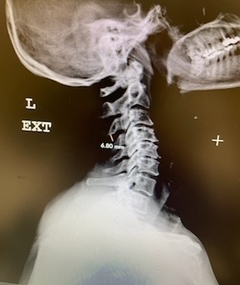

(2b) Lateral Flexion cervical x-rays extension image demonstrating 8mm of splaying of the C34 interspinous distance.

The fluid was possibly consistent with CSF versus chronic hematoma. The patient was also noted to have a high signal within the interspinous space of C3-C4. This high signal was consistent with a ruptured C3-4 interspinous ligament. Cervical flexion-extension x-rays demonstrated 6 mm of widening of the C3-4 interspinous space on flexion x-ray consistent with cervical instability (Fig. 2a and 2b).